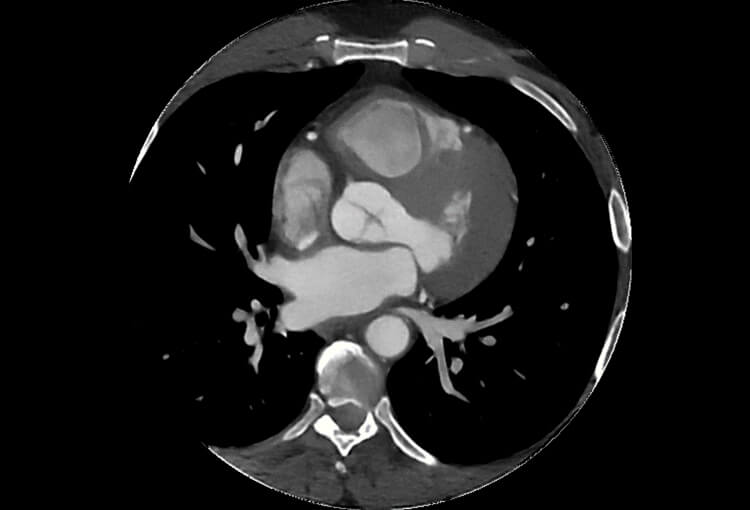

120 kV / 30 mAs / 1mm

Before FBP (Noise 150) VS After ClariCT.AI (Noise 49) 67% Denoising